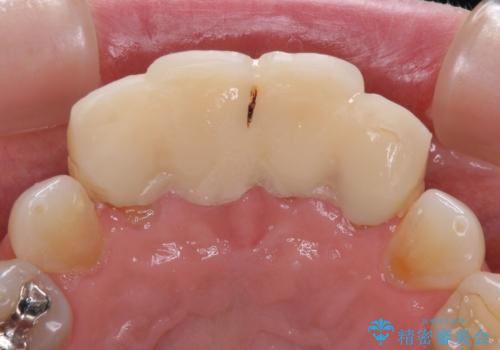

- 自宅近くの歯科医院にて前歯の詰め物が外れたことを機会に、オールセラミッククラウンへの変更を決断して4歯を仮歯に替えたものの、あまりに汚くて恥ずかしいとのことで来院された患者様です。

歯の形成量は不十分で形態は不自然、境目は不適で歯肉が腫れていたため、新しい仮歯に替えた後に歯肉の腫れが引くのを待ち、オールセラミッククラウンにて補綴することとしました。